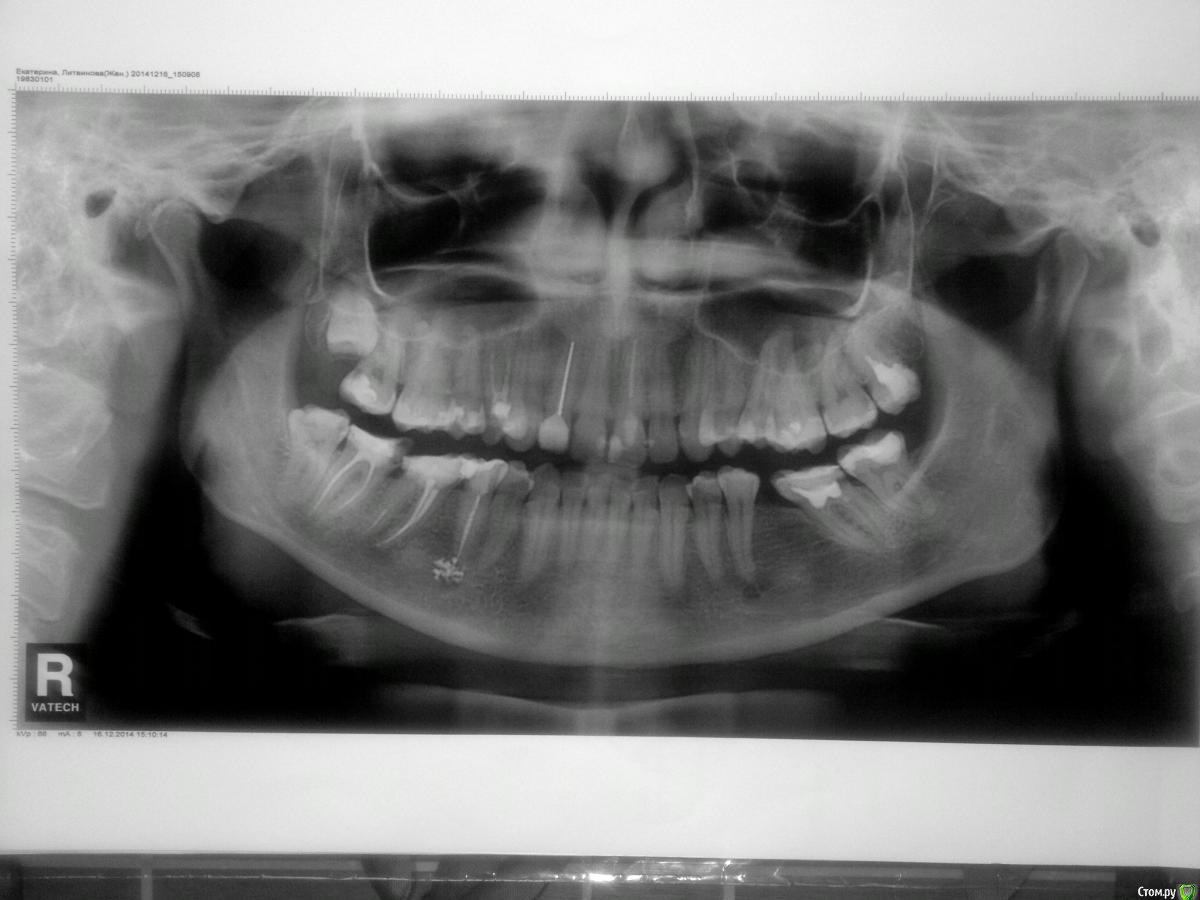

Екатерина Литвинова Опубликовано 16 марта, 2015 Автор Поделиться Опубликовано 16 марта, 2015 (изменено) Прикрепляю панорамный снимок,сделанный в декабре 2014,перед удалением зуба мудрости Изменено 16 марта, 2015 пользователем Екатерина Литвинова Ссылка на комментарий